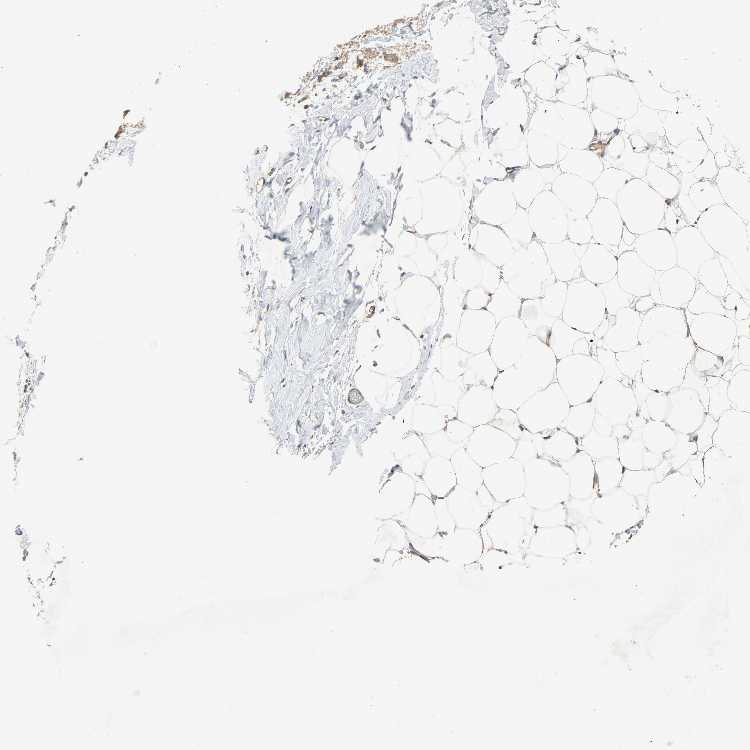

TISSUE PRIMARY DATA SOFT TISSUE Show tissue menu

SOFT TISSUE - Expression summary

SOFT TISSUE 1 - Antibody stainingi

Antibody staining in the annotated cell types in the current human tissue is reported as not detected, low, medium, or high, based on conventional immunohistochemistry profiling in selected tissues. This score is based on the combination of the staining intensity and fraction of stained cells.

Each image is clickable and will lead to virtual microscopy that enables deeper exploration of all samples and also displays staining intensity scores, fraction scores and subcellular localization as well as patient and tissue information for each sample.

Antibody HPA007478Antibody HPA007966

Fibroblasts LowNot detected

Peripheral nerve Not detectedLow

SOFT TISSUE 2 - Antibody stainingi

Fibroblasts Not detectedNot detected